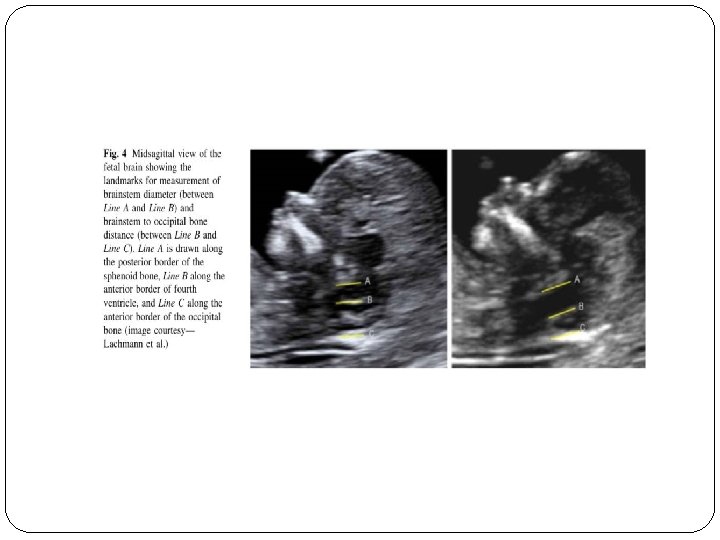

IT(Intracerebral Translucency )

IT…. open NTD �One of the major failings of the first trimester fetal ultrasound examination had been the inability to consistently diagnose open neural tube defects other than the exencephaly/ anencephaly sequence �A recently described intracranial marker [intracerebral translucency (IT)] may overcome this deficiency. � The fetal image required to evaluate the IT is identical to those needed for the NT, NB and FMF angle evaluation

� A magnified midline view of the fetal head and upper thorax is obtained and the following intracranial structures need to be visualized: hypoechoic regions of the thalamus, the pons (brain stem) and the medulla oblongata � The IT represents the fluid filled fourth ventricle, which is located posteriorly to the pons. � The combination of the posterior border of the pons and the floor of the fourth ventricle is seen as a single thin echogenic line, which forms the anterior border of the IT. � The posterior border of the IT is the roof of the fourth ventricle. This is seen also as a relatively thin

� The proposed mechanism for this finding is similar to that of the Chiari type II malformation (banana sign) seen in second trimester fetuses with spina bifida aperta: decreased pressure in the subarachnoid spaces leading to the caudal displacement of the brain. � Measuring the IT does not provide additional information. Therefore, the IT is simply reported as present or absent. � It would be premature to state that the absence or presence of IT has the same predictive value as the intracranial findings in the second trimester. However, the absence of the IT should lead to an extremely careful ultrasound evaluation of the spine at the time of the first trimester ultrasound. If the appearance of the spine is normal on the initial scan, the fetus should be reexamined at approximately 16 weeks. A 20 week scan should also be performed if the 16 week scan is normal.

� So normally, the ratio of the BS to the BSOB will range from 0. 8 at 11 weeks to somewhere around 0. 7 at 14 weeks. In fetuses with open spina bifida, because of the posterior shift of the brain, the BS appears relatively enlarged and shifted backwards, so the BS to BSOB (BS/ BSOB) ratio is increased and it is usually more than one